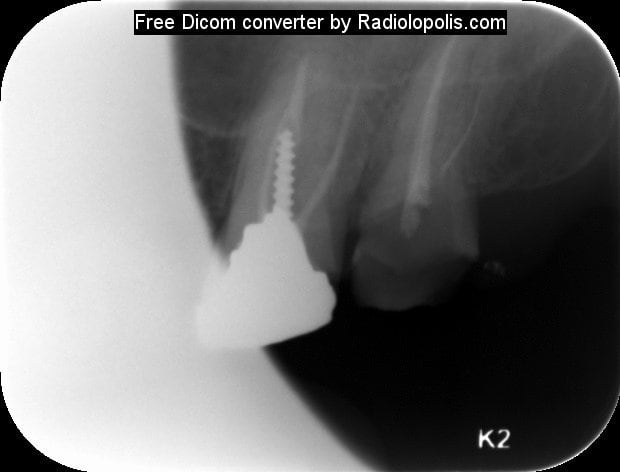

Comme promis voilà les radios .... Pas fier je suis.

Radiolopolis 1 pqzmoo - Eugenol

Radiolopolis 2 lnls6d - Eugenol

Radiolopolis mtbhfu - Eugenol

pfffffffffffff !!! franchement ce ne sera pas tres difficile pour toi de retirer cet instrument, tu prends une lime K 15 ou 10 et tu tentes de passer à coté tout en la plaquant contre l'instrument au moment du retrait (Ne force pas ta lime sinon deuxieme fracture!!!). tu irrigues beaucoup (avec de l'EDTA c'est encore mieux)jusqu'au moment où tu sentiras ton instrument se libérer.

Le RTE est possible mais difficile!

Autrement après retouche cavité d'accès+digue et effectivement utilisations de la techique by pass+éventuellement utilisation des kits genre Komet rescue pour tenter d'enlever le NITI+ultrasons+utilisations des loupes ou mieux microscope opératoire.Il y a un risque de faire un faux canal avec le bi pass.Je confirme ,il faut au moins une heure trente pour finir l'endo ,mais c'est certainement plus tranquille pour un endo exclusif.